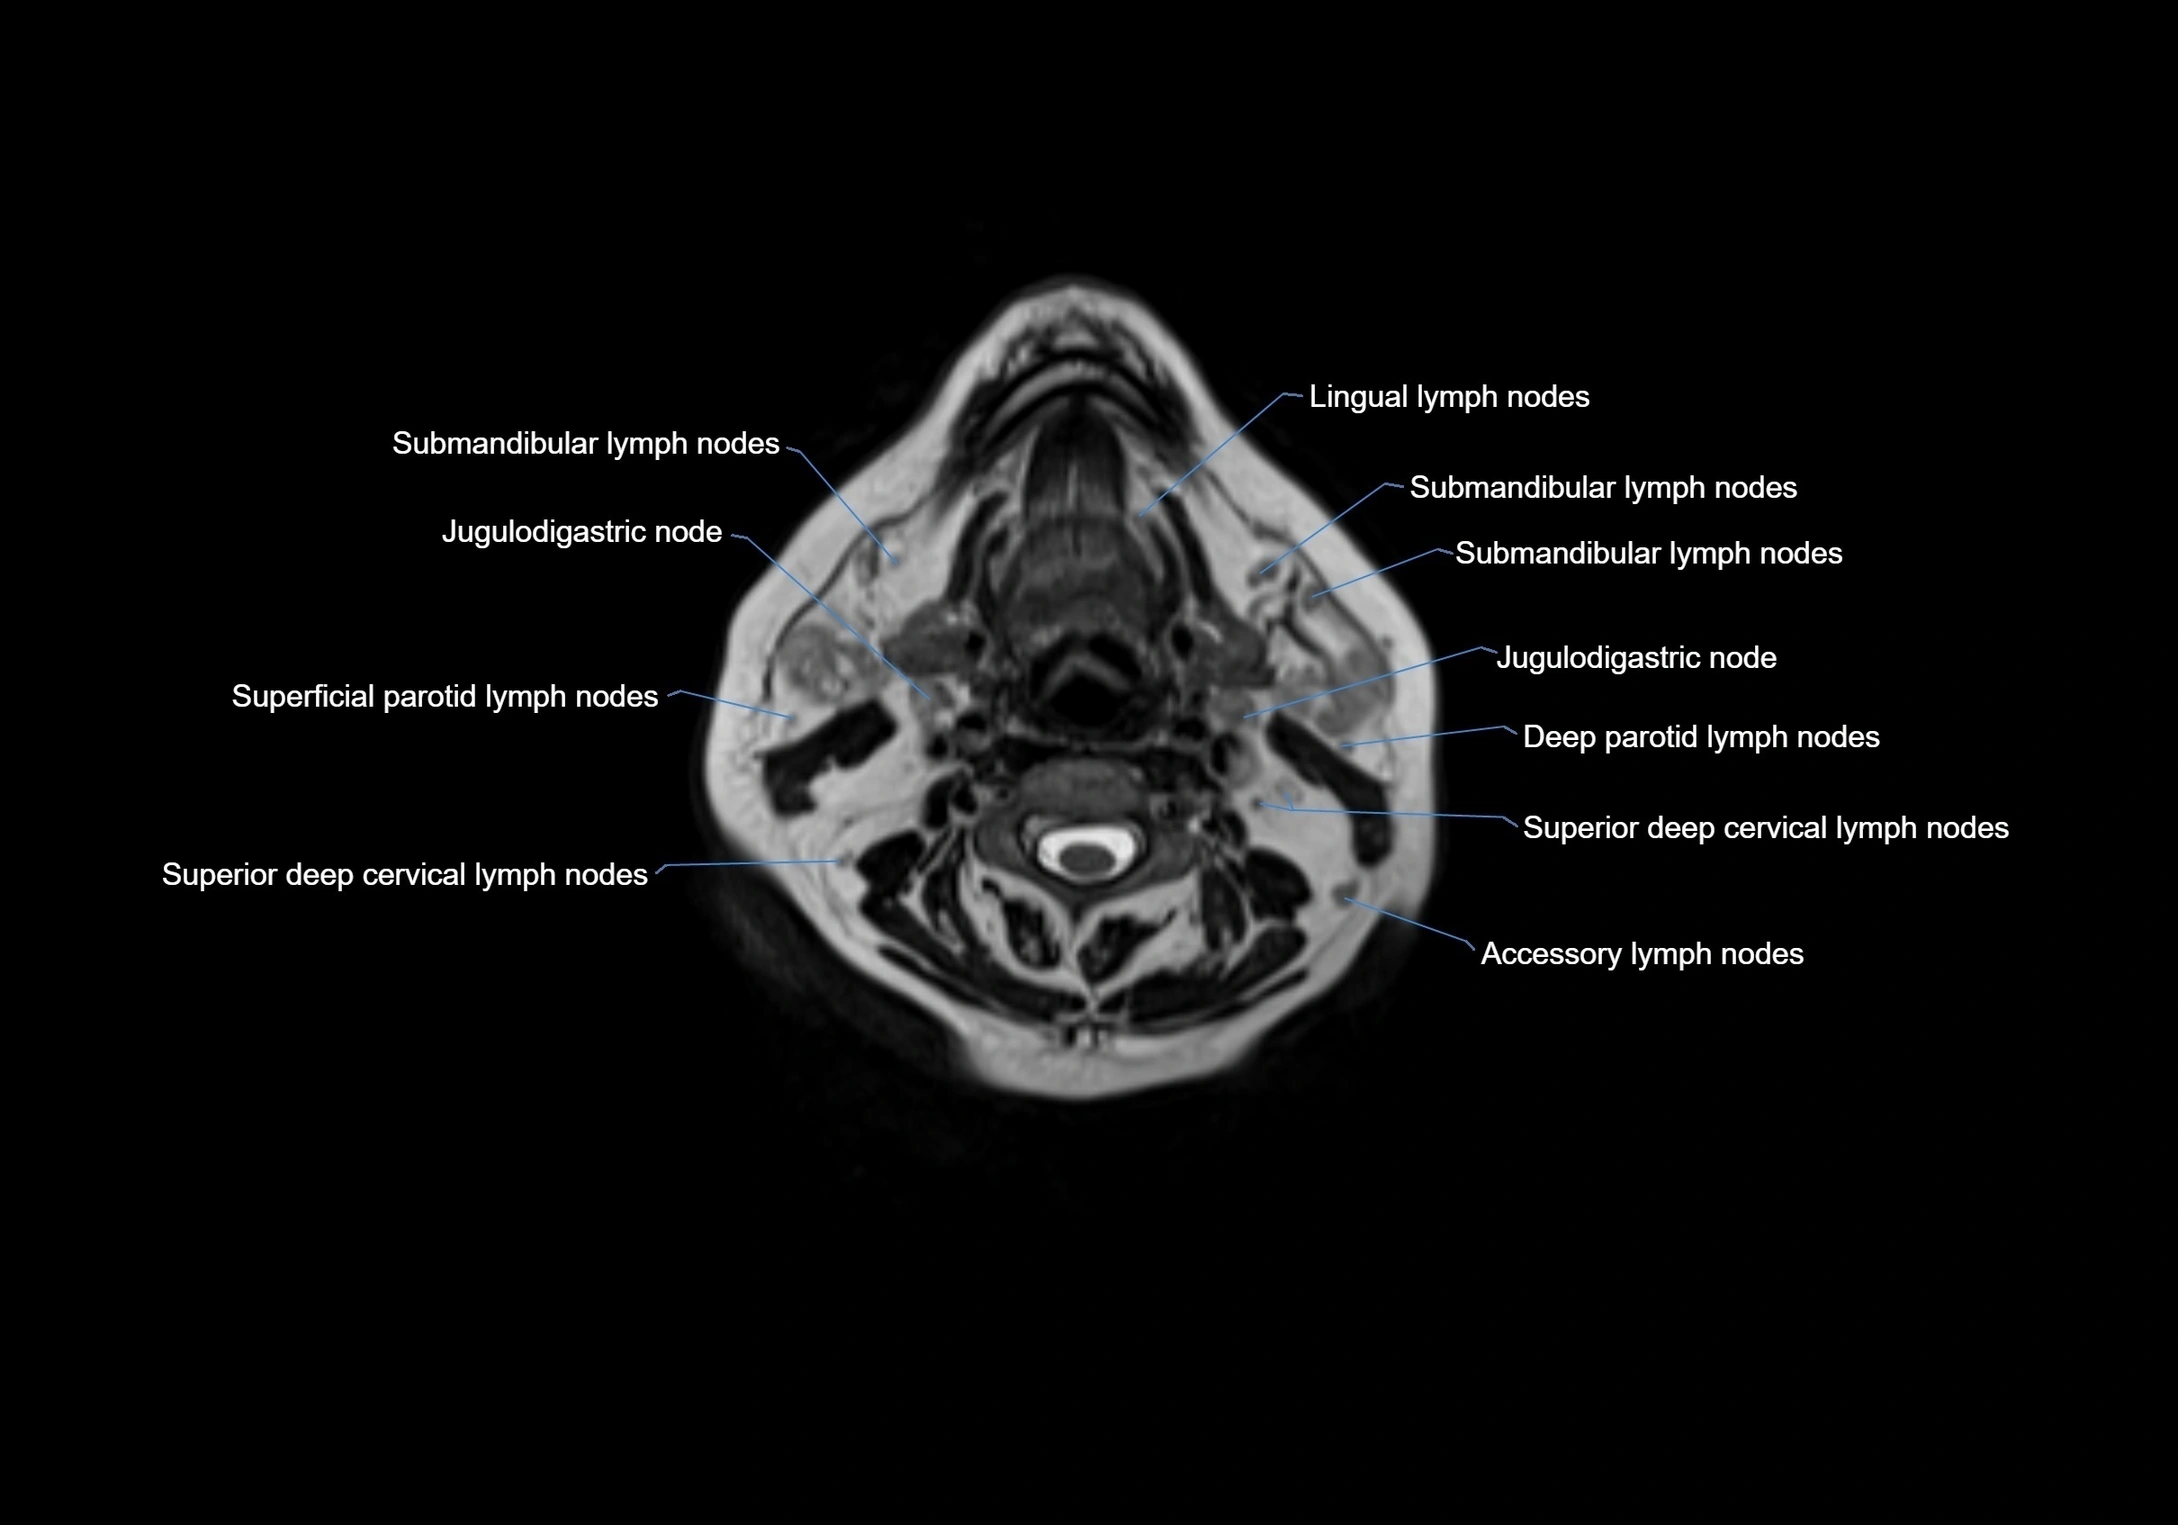

Location

• Found along primary lymph node chains, including preauricular, submandibular, parotid, and occipital regions

• Embedded in subcutaneous fat or superficial fascia, often lateral or posterior to primary nodes

• Variable in number; may occur unilaterally or bilaterally, depending on individual anatomy

MRI images

image